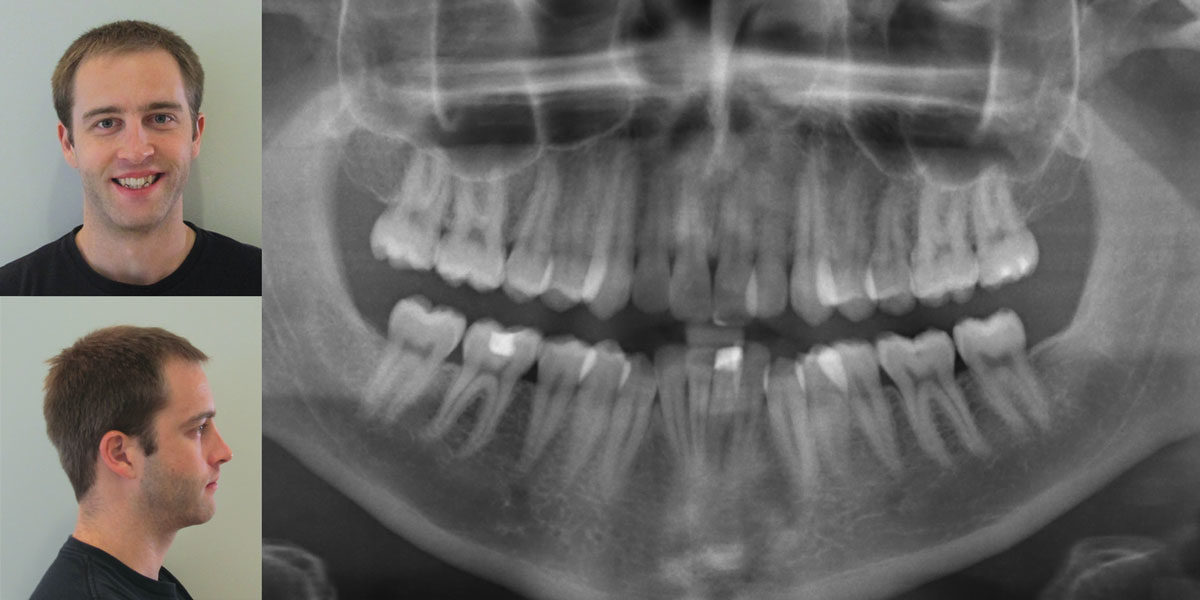

Read ColumnDr. Larry W. White examines a common outcome of the removal of maxillary and mandibular premolars in Class II malocclusions Abstract Dr. Charles Tweed had enormous influence in orthodontics by developing a rationale for the extraction of premolars and the Tweed Triangle, which he used as a diagnostic and treatment-planning instrument. He used the premolar